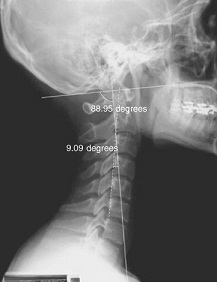

À̰޼.... ¾çŰ ÀÇÇпë¾î·Î´Â... Craniocervical radiographic tracingÀ̶ó°í Çϸç.. ±¹»ê ÀÇÇпë¾î·Î´Â...¤Ñ¤Ña....µÎ°³°æºÎ¹æ»ç¼±ÃßÀû»çÁøÀ̶ó ÇÑ´Ù..